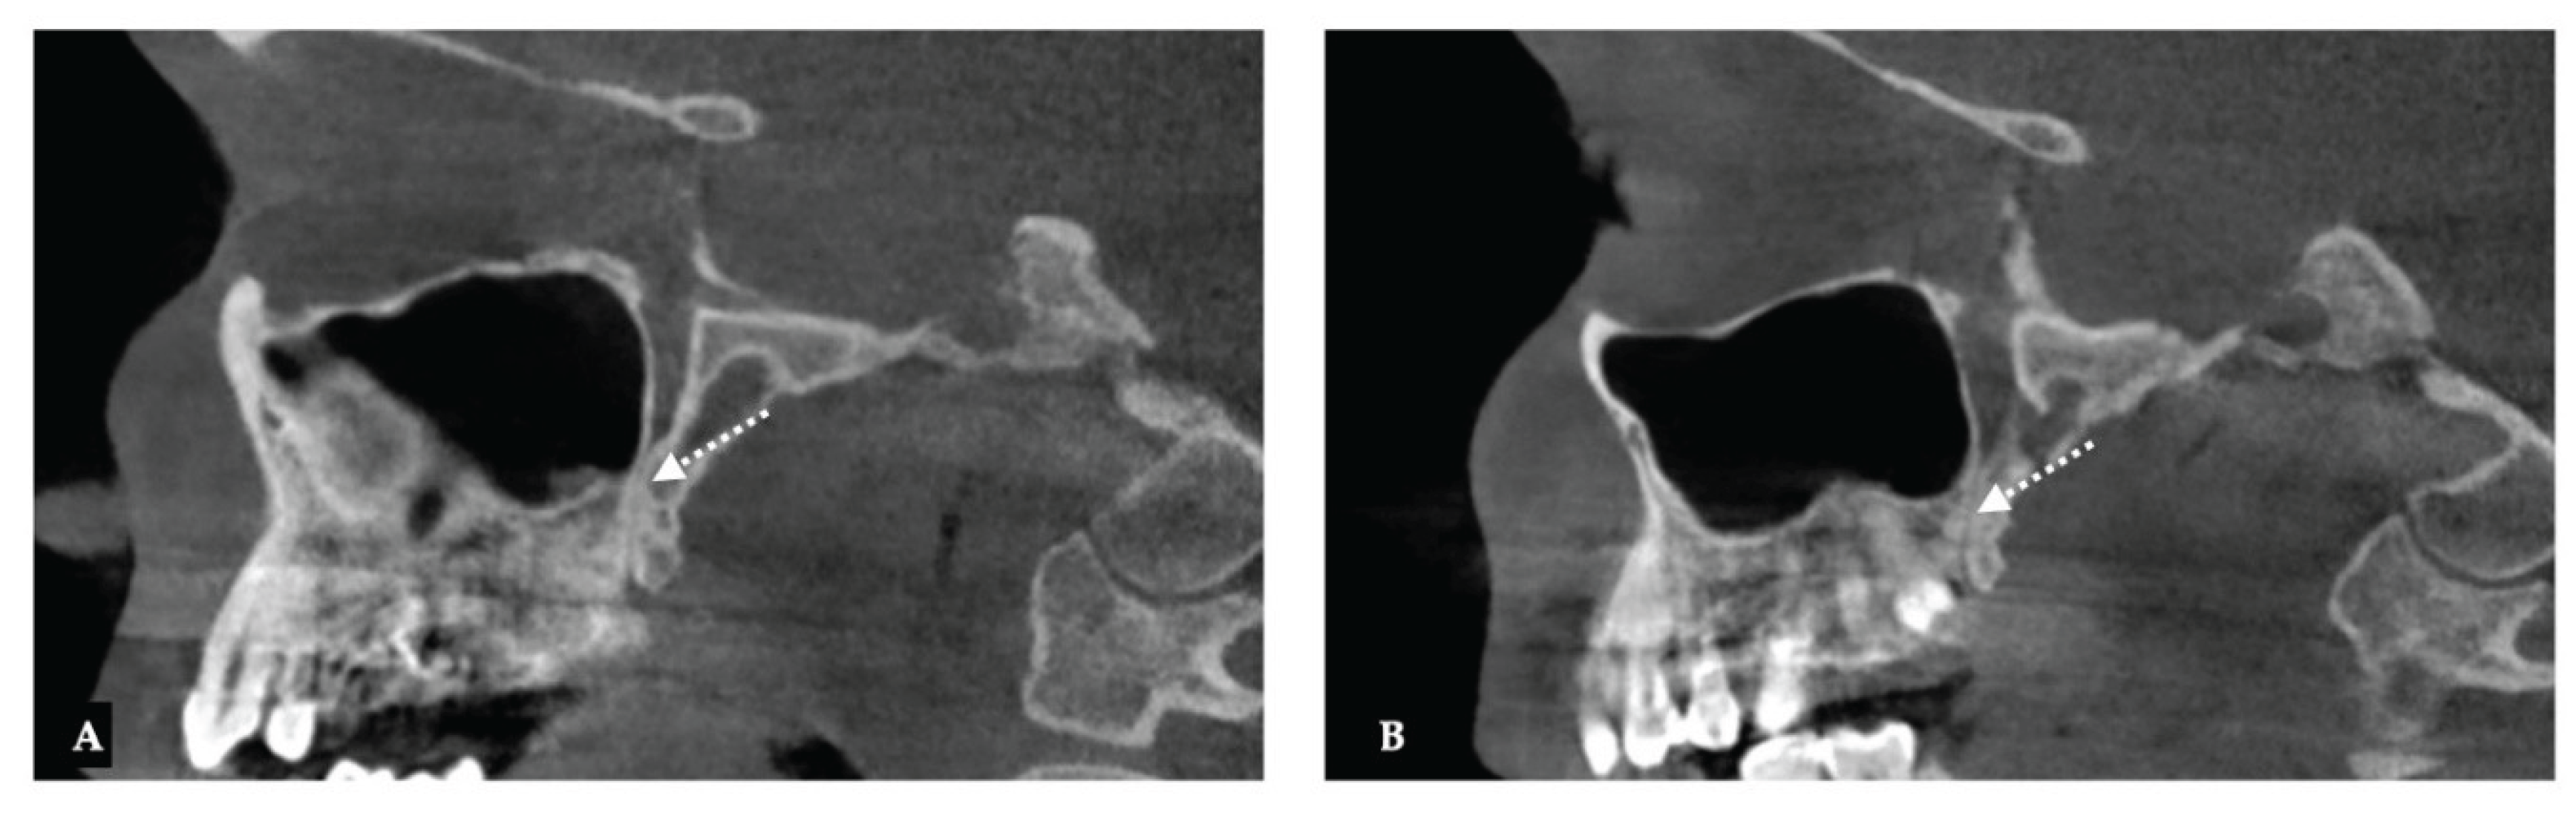

Background: While mini-screw-assisted rapid palatal expansion (MARPE) is effective for correcting maxillary transverse deficiency in adults, perimaxillary suture disarticulation—particularly at the pterygomaxillary junction—can be inconsistent. This study evaluates skeletal and dentoalveolar outcomes of a novel 3D-guided midpalatal piezocorticotomy-assisted MARPE protocol, focusing on expansion symmetry and pre-existing asymmetries. Methods: Three adult patients were retrospectively analyzed after treatment with 3D-guided midpalatal piezocorticotomy-assisted MARPE expansion and one with non-guided midpapalatal piezocorticotomy and MARPE expansion. Surgical guides were digitally designed using CBCT data to align with the nasal septum orientation in multiple planes. Perimaxillary suture disarticulation was measured pre- and post-expansion, and dentoalveolar changes were evaluated. Post-expansion asymmetries were addressed using directly printed aligners. Results: Complete midpalatal suture separation (mean 8.48 mm), involving both anterior and posterior nasal spine regions, was achieved in one patient. Bilateral pterygomaxillary disarticulation averaged 1.06–1.23 mm, resulting in forward–outward rotation of the nasomaxillary complex. Additional separation occurred at the frontonasal (2.03 mm) and vomeromaxillary (1–2 mm) sutures, with no significant changes in orbital or peri-orbital sutures. One patient presented with pre-existing dentoalveolar asymmetry, which intensified the perceived post-expansion imbalance but was successfully corrected with directly printed aligners. In the second case, 5.6 mm of suture separation resulted in a limited lateral nasal width increase (<1.5 mm), while maxillary base expansion exceeded 6 mm. A significant canine plane cant (1.2 mm) and divergent axial inclinations of the maxillary central incisors relative to the palatal plane were also observed. In the second case, a non-impactful palatal bone fracture with asymmetric displacement of the left palatine fragment was documented. After 16 months of aligner therapy, all cases exhibited favorable remodeling of the palatal structures, midpalatal suture, and alveolar processes, accompanied by improved dental alignment, occlusal plane symmetry, and mandibular dentoalveolar adaptation. The dento-alveolar expansion achieved in the third case over the course of 16 months of treatment was approximated at 4 mm. The fourth case showed consistent improvement with direct printed aligners after MARPE midpalatal diasrticulation of 11 mm after experiencing minor bone fracture. Conclusions: Human skulls exhibit considerable variability between the left and right sides, which can influence spatial balance. Pre-existing cranial asymmetries appear to be the primary contributors to asymmetry following MARPE treatment. Careful evaluation of dentoalveolar discrepancies and axial tooth inclinations is essential for preventing and managing potential asymmetric dental arch outcomes during the post-expansion phase. Although peri-maxillary bone fractures are relatively uncommon, their occurrence is influenced by multiple factors. Adjunctive techniques, such as 3D-guided midpalatal piezocorticotomy, show promise in significantly lowering the risk of intra-expansion peri-maxillary fractures.

| Suture nomenclature | Amount of disarticulation |

|---|---|

| Pterygomaxillary | 1.06-1.23 mm |